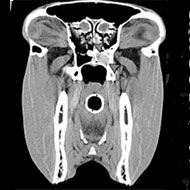

Advanced diagnostic techniques are also assisting with clinical and surgical approaches to problems with the equine head. Owing to its position, the sphenopalatine sinus is challenging to assess radiographically but CT can help to overcome this. One study looked at how CT can help to unravel the pathology of various equine sinonasal tumours.

CT is also useful for identifying defects in the bone and tooth, according to a study of horses with diseased mandibular cheek teeth, but is far less beneficial in identifying inflammation and tissue destruction - which is better served by MRI.

Images supplied by Bright bay Consulting from the paper: ‘The role of the head computed tomography in equine practice’.